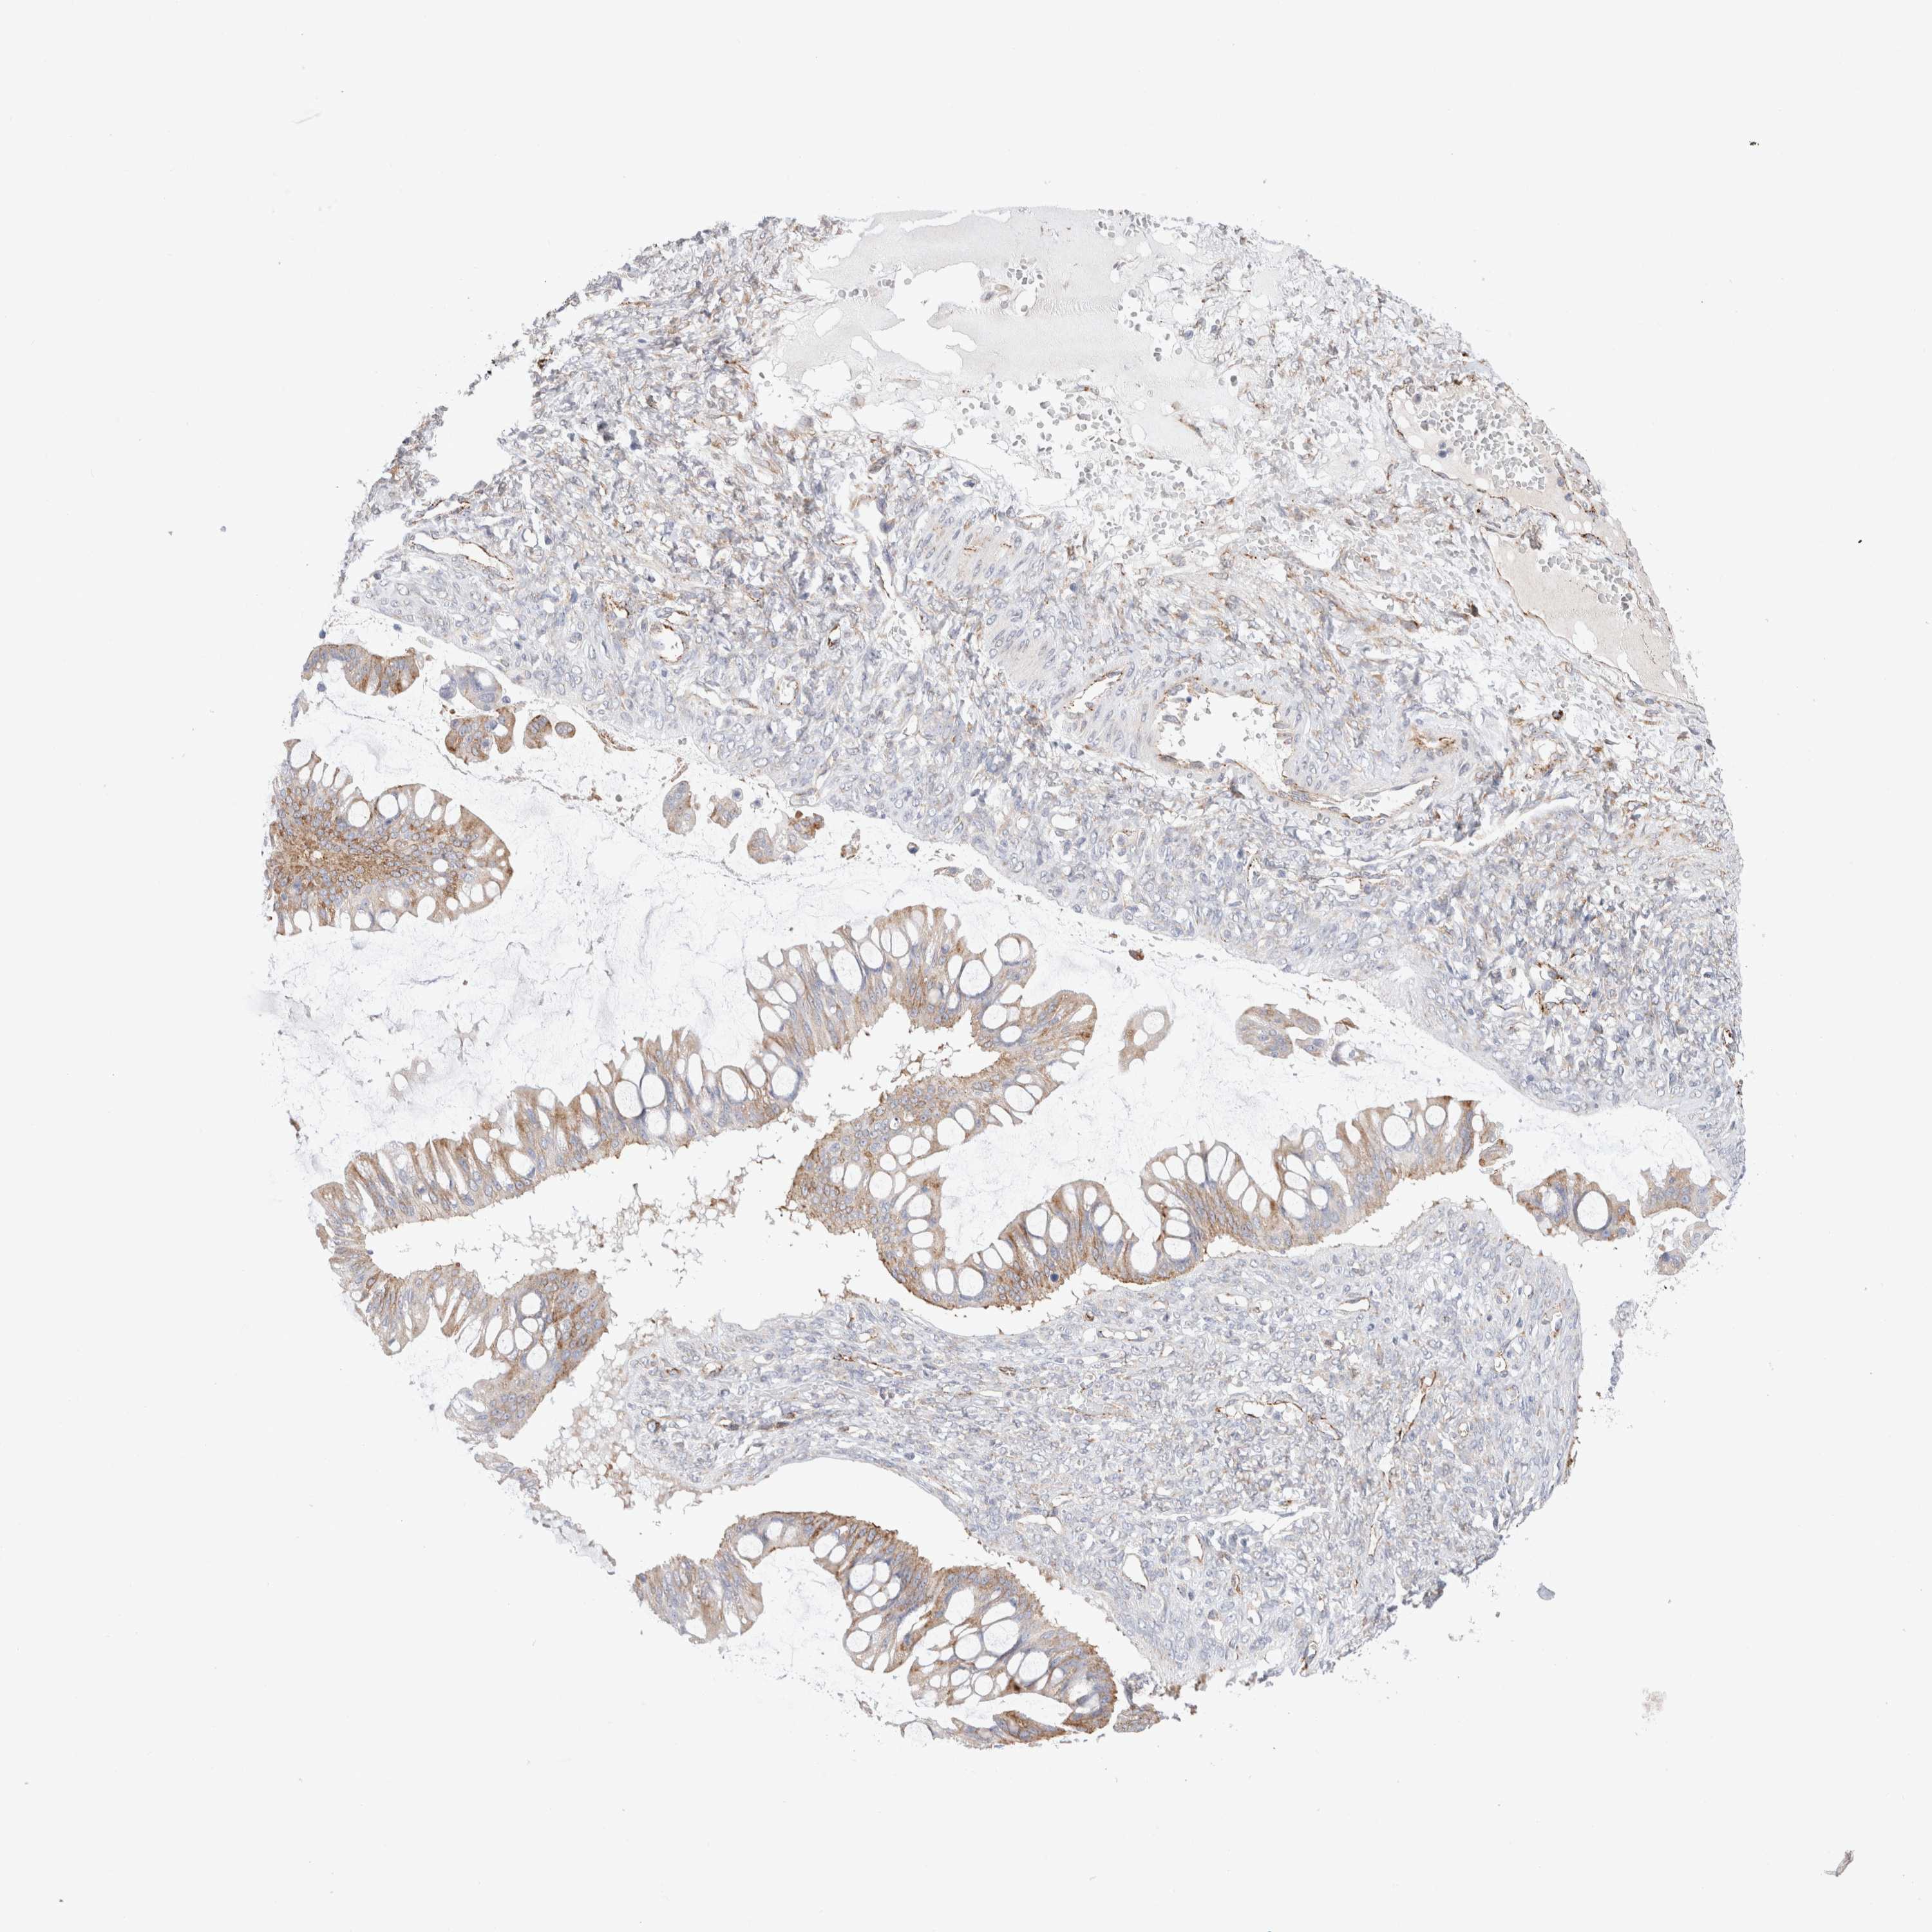

OVARIAN CANCER - Protein expressioni

A mouse-over function shows sample information and annotation data. Click on an image to view it in a full screen mode. Samples can be filtered based on level of antibody staining by selecting one or several of the following categories: high, medium, low and not detected. The assay and annotation is described here.

Note that samples used for immunohistochemistry by the Human Protein Atlas do not correspond to samples in the TCGA dataset.

Antibody stainingi

Antibody staining in the annotated cell types in the current human tissue is reported as not detected, low, medium, or high, based on conventional immunohistochemistry profiling in selected tissues. This score is based on the combination of the staining intensity and fraction of stained cells.

Each image is clickable and will lead to virtual microscopy that enables deeper exploration of all samples and also displays staining intensity scores, fraction scores and subcellular localization as well as patient and tissue information for each sample.

Antibody HPA014166

Antibody HPA025240

Cystadenocarcinoma, serous, NOS

Carcinoma, endometroid

Cystadenocarcinoma, mucinous, NOS

Carcinoma, NOS